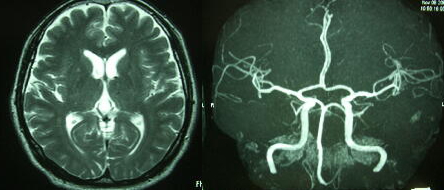

はい、今日のメインイベント。 本当はPETとも思ってみたのだが、安くても10万円くらいするようだし、放射性物質を体の中に注射するみたいなので・・・。ただでもCTでたくさん放射線を浴びているのと、やはり注射嫌いの私にはとても耐えられそうにないということもPETよりMRIを選んだ大きな理由だ。

MRI&MRAは時間がかかる